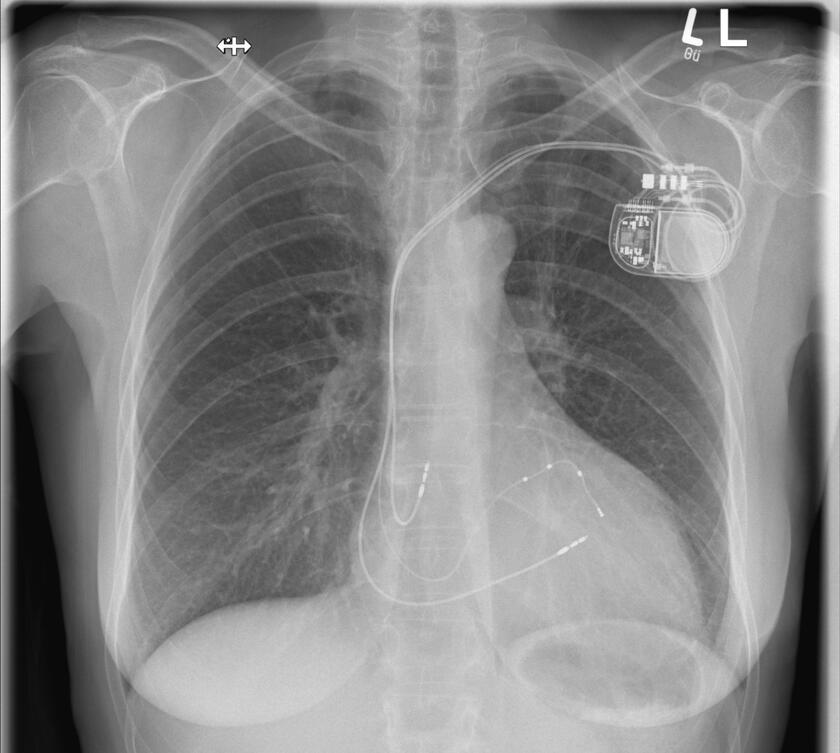

Wenn das Herz zu langsam schlägt, dann spricht man von einer Bradykardie. Diese ist meistens behandlungsbedürftig, denn sie kann zu Ohnmachtsanfällen (Synkopen) und im schlimmsten Fall zu einem Herzstillstand führen. Wenn sich keine behebbare Ursache finden lässt, ist die Implantation eines Herzschrittmachers die Therapie der Wahl. Der Schrittmacher regt den Herzmuskel mit leichten nicht spürbaren elektrischen Impulsen zum regelmäßigen Schlagen an. Der Herzschrittmacher wird in der Regel im Brustbereich unterhalb des Schlüsselbeines eingesetzt. Der kleine Eingriff erfolgt unter lokaler Betäubung während eines kurzen stationären Aufenthaltes oder auch ambulant. In unserer Klinik werden alle gängigen Systeme implantiert. Gerne informieren wir Sie in unserer Sprechstunde über weitere Einzelheiten. Hier erfolgt auf Wunsch auch die Nachsorge der implantierten Geräte (Sprechstunde).

Defibrillator

Die Implantation eines Defibrillators (ICD) erfolgt in der Regel bei einem erhöhten Risiko für gefährliche Herzrhythmusstörungen oder nach einem überlebten plötzlichen Herztod (SCD). Ein elektrischer Schock sorgt beim Auftreten einer entsprechenden Rhythmusstörung dafür, dass ein aus dem Takt geratenes Herz wieder richtig schlägt und die lebensbedrohliche Situation beendet wird. Die allermeisten Defibrillatoren haben zusätzlich die Funktion eines Herzschrittmachers. Ähnlich wie ein Herzschrittmacher wird das ICD-Gerät im Brustbereich unterhalb des Schlüsselbeines unter lokaler Betäubung eingesetzt. In unserer Klinik werden alle gängigen Systeme implantiert. Gerne informieren wir Sie in unserer Sprechstunde über weitere Einzelheiten. Hier erfolgt auf Wunsch auch die Nachsorge der implantierten Geräte (Sprechstunde).

Bei einer Herzmuskelschwäche pumpt der Herzmuskel häufig nicht mehr synchron. Aus diesem Grund kann es sinnvoll sein, diese „Asynchronie“ durch die Implantation zusätzlicher Stimulationssonden wieder zu beheben. Diese Sonden können die linke Herzkammer, aber auch direkt das Reizleitungssystem stimulieren. Eine solche kardiale Resynchronisationstherapie kann als reine Herzschrittmacherimplantation, aber auch in Kombination mit einem Defibrillator erfolgen. Grundsätzlich läuft die Operation wie die Implantation eines Herzschrittmachers ab, kann jedoch aufgrund der zusätzlichen Sonde(n) etwas länger dauern.